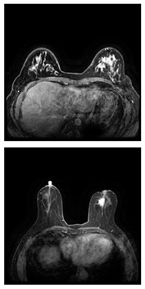

Table 11 presents a comparison between the mask images generated using three different frameworks and the ground truth masks for image segmentation. In Table 12, the performance comparison of various models on the BUSI and BreastDM datasets is presented, emphasizing their respective performance metrics. The methods for calculating performance metrics are detailed in Appendix A.

Table 11.

Comparison of different models using datasets.

For the BUSI dataset, the U-KAN model demonstrates superior performance across most metrics relative to U-Net and U-Net++. Specifically, U-KAN achieves the highest accuracy (0.933), precision (0.754), and F1 score (0.747). Additionally, it records the highest specificity (0.963) and AUC (0.935), although its recall (0.740) is marginally lower than that of U-Net++ (0.749). These results indicate that U-KAN offers balanced and robust performance, excelling particularly in accuracy and specificity, which are critical for reliable image segmentation.

Regarding the BreastDM dataset, all three models exhibit high accuracy, yet U-KAN again shows the best overall performance. U-KAN achieves the highest accuracy (0.986), recall (0.870), F1 score (0.728), specificity (0.993), and AUC (0.838). In comparison, U-Net++ demonstrates slightly lower performance with an accuracy of 0.985 and an AUC of 0.822, while U-Net exhibits an accuracy of 0.983 and an AUC of 0.815.

These findings suggest that U-KAN is particularly effective for image segmentation tasks, especially in the context of early breast cancer diagnosis. It provides superior accuracy, specificity, and balanced performance across other metrics compared to U-Net and U-Net++, thus offering enhanced capabilities for detecting early-stage breast cancer lesions. Consequently, U-KAN’s advanced performance metrics underscore its potential as a reliable model for clinical applications in breast cancer detection.